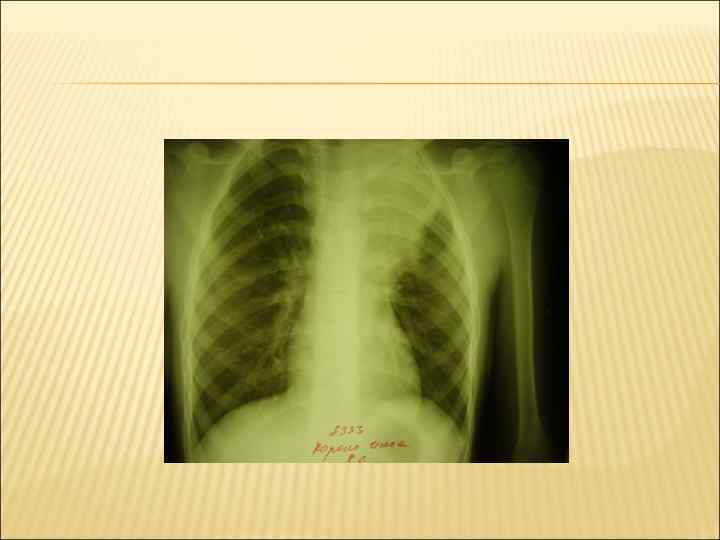

КРУПОЗНАЯ ПНЕВМОНИЯ. Термин « крупозная пневмония» используется в русской медицинской литературе, и ввел его С. П. Боткин для выделения больных с тяжелым течением долевой пневмонии со стонущем дыханием Бурное начало, гипертермия, озноб, резкая головная боль головокружение Кашель сначала отсутствует или сухой, редкий Выраженный токсикоз, ДН, абдоминальный синдром, при осмотре: заторможенность, бледность кожных покровов с румянцем щек ( чаще на стороне повреждения) Цикличность течения: